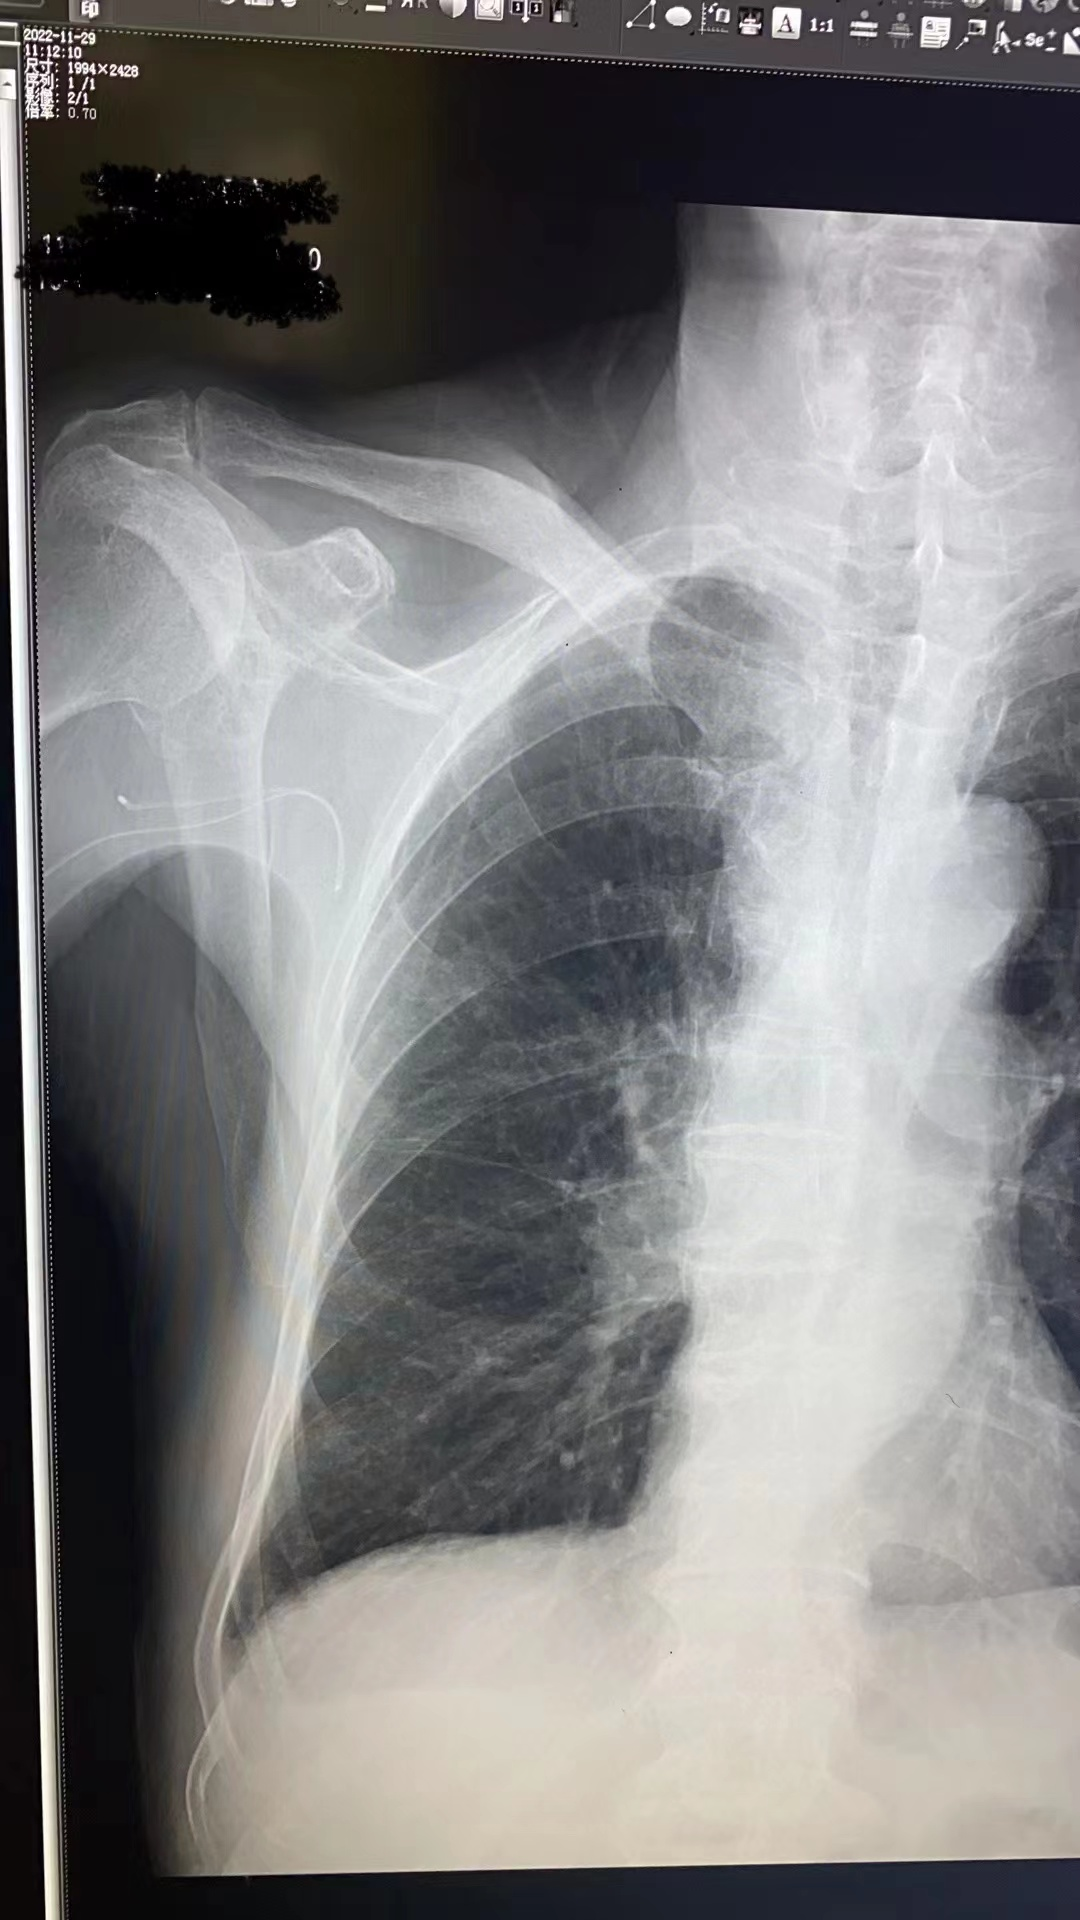

事情要从高大伯因“左肺恶性肿瘤”住院说起,医生分析了病情为其制定治疗方案——化疗。在治疗开始前需要进行经外周静脉穿刺中心静脉置管术(PICC),静疗专项小组组长冯尼尼和外科徐锦艳护士长在充分评估患者病情及血管条件后为高大伯进行PICC穿刺,穿刺过程很顺利,但在导管置入25cm时,遇到阻力,置入后回弹,出现置管困难,在反复多次调节体位,边冲管边置管等多种尝试下,成功置入。半小时拍片定位显示,患者PICC导管位于右侧腋窝区,导管在右锁骨下静脉返折。考虑原因:血管畸形、官腔狭窄、肿瘤站位压迫血管等,再次调整重新置管,出现导管反折致导管异位的概率很高。